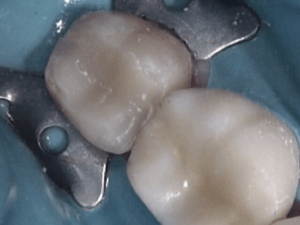

Before and After Treatments

Gordon Street Dental Success Stories in Guelph

Many Patients have allowed us to show what we’ve done for them. Please feel free to look at what we’ve done for them, as well as envision what we can do for you.

Image Grid Title